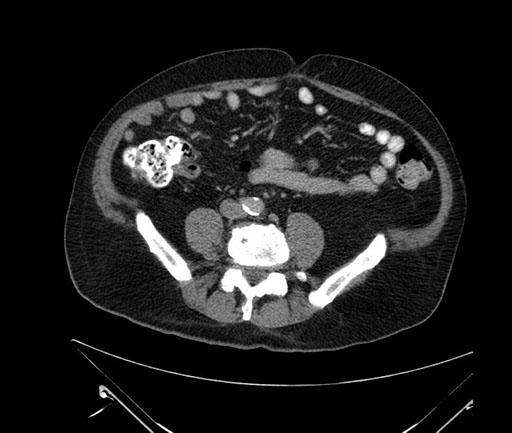

Axial - 3 months prior